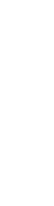

보철치료

보철치료

보철치료

치아의 일부 상실된 부분을 정상적인 모양으로 회복시켜주며 인레이, 크라운, 브릿지 등 보철 수복을 통해 자연치아를 보호하고 재건을 돕습니다.